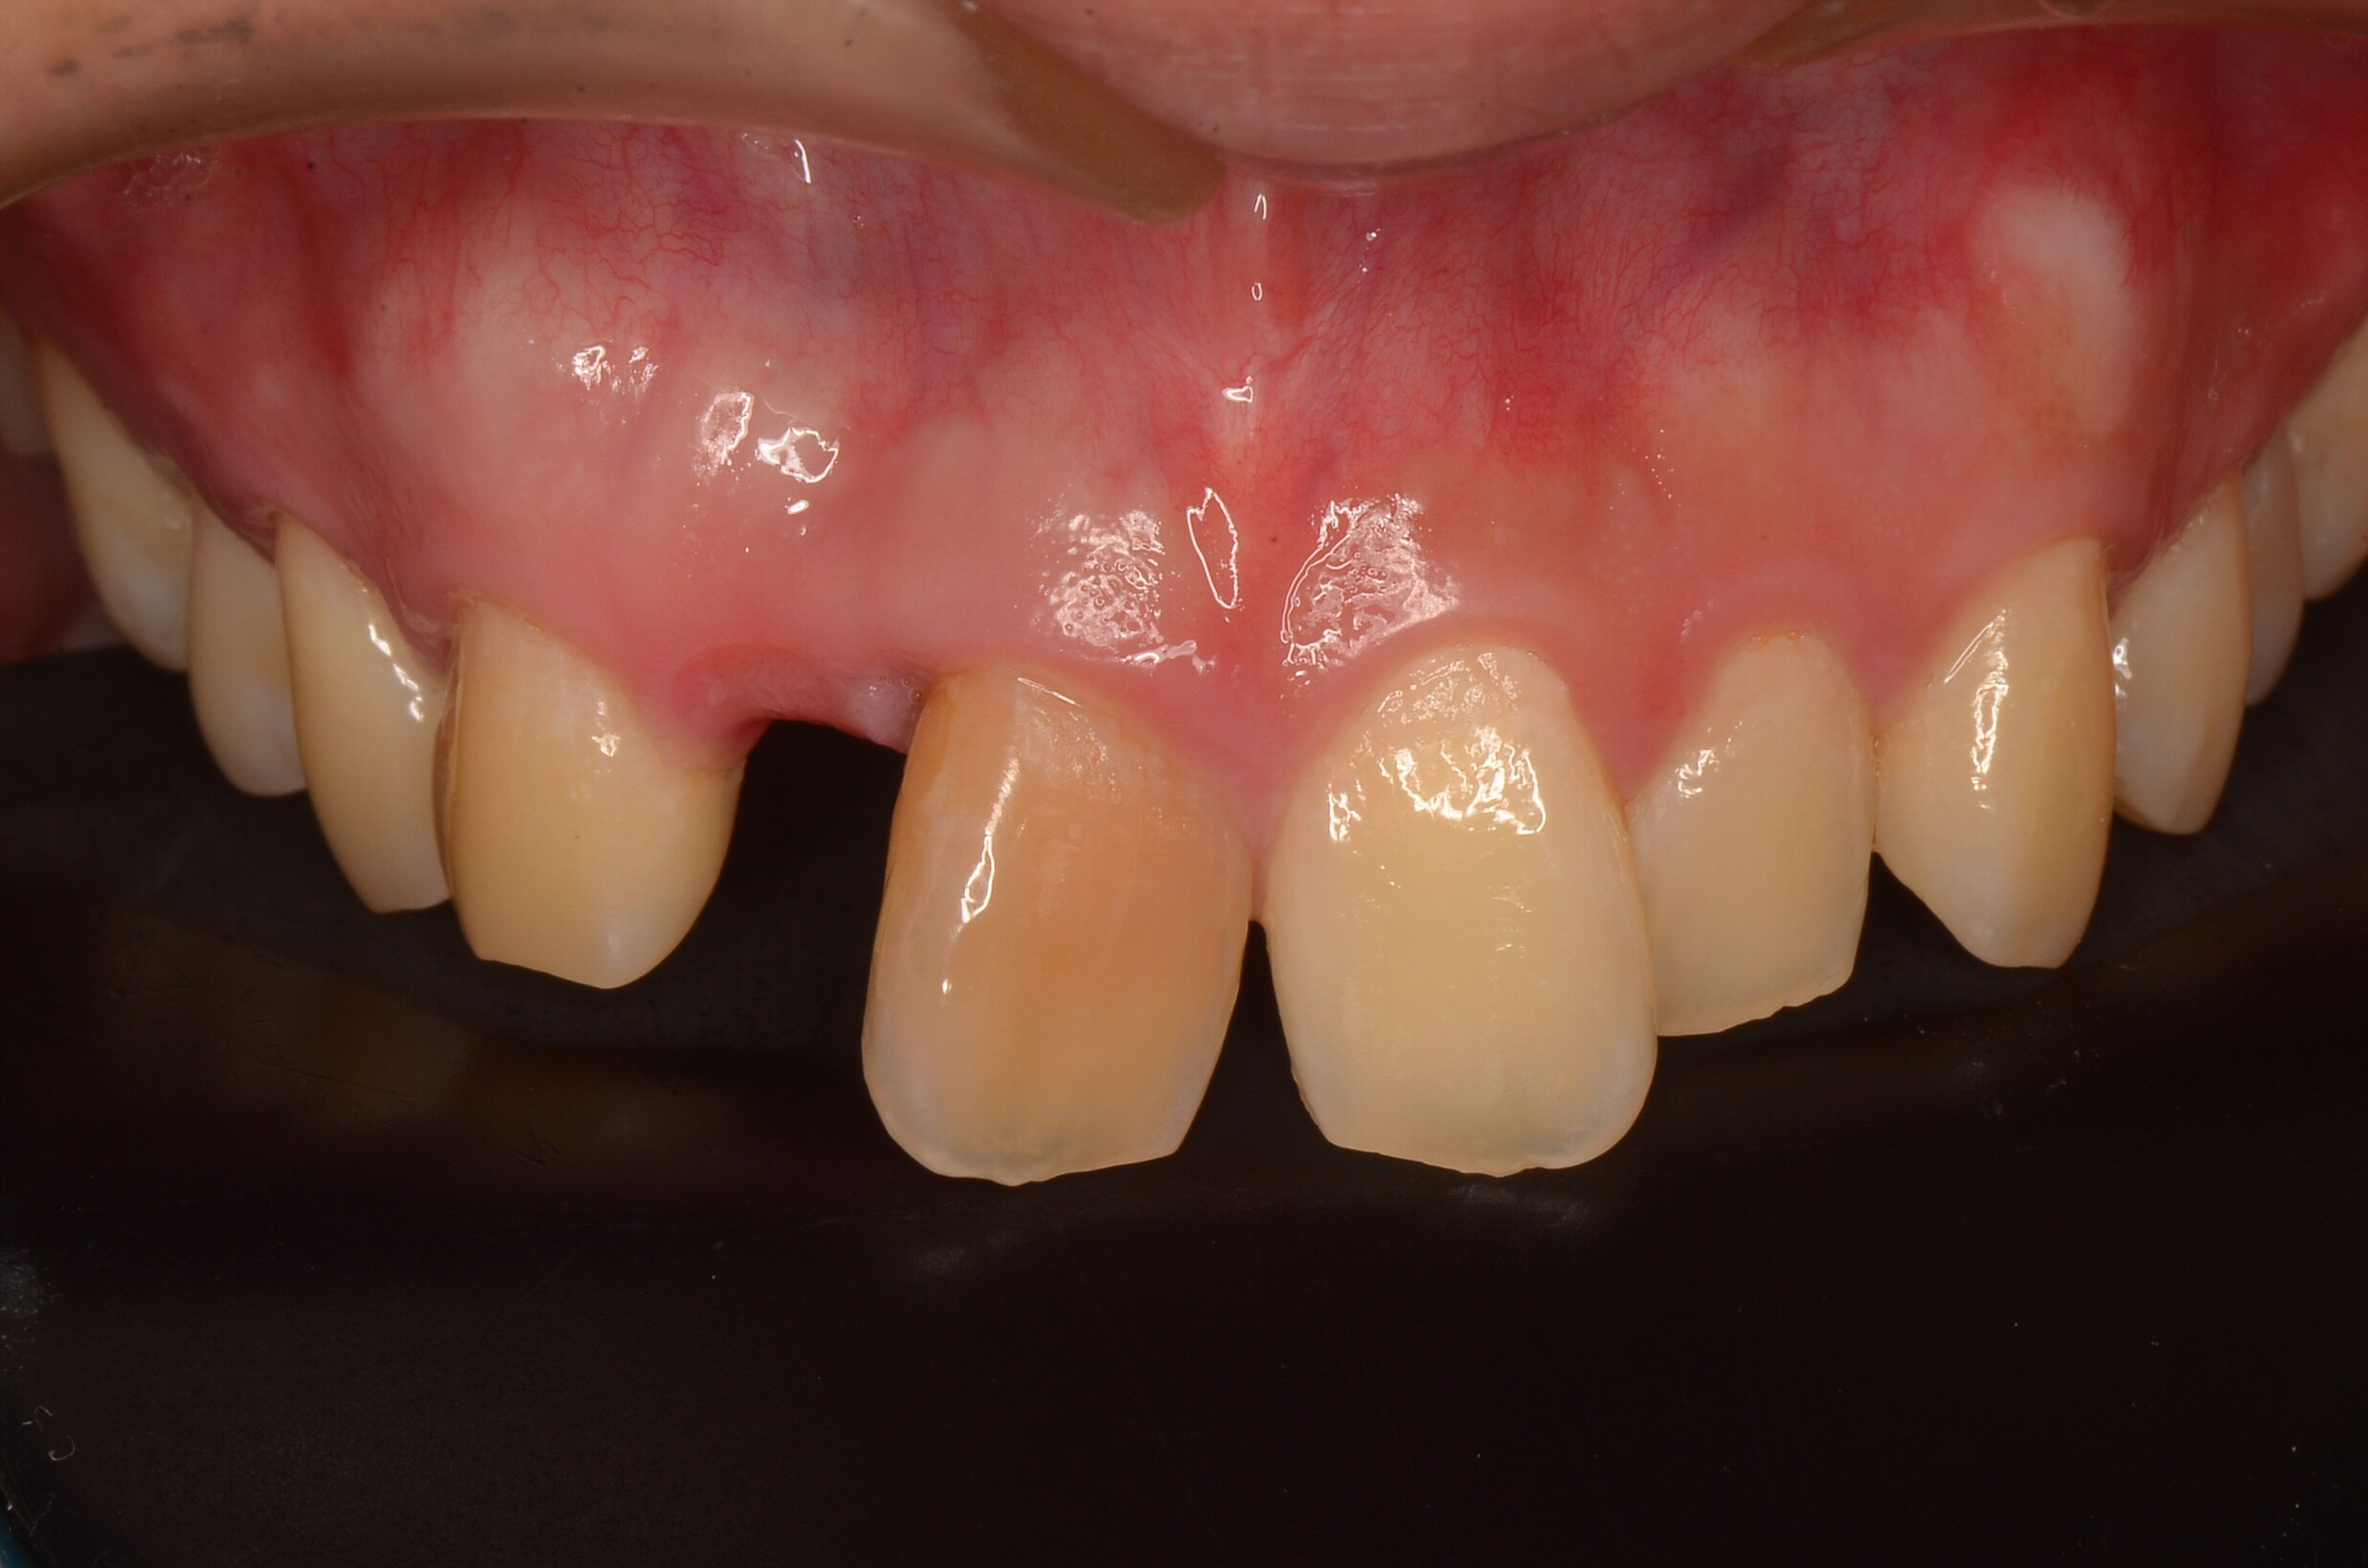

補綴(セラミック)

Before

After

年齢

22歳

主訴

外傷で前歯が抜けた

治療期間

約3ヶ月

治療費

約450,000円

概要

外傷により前歯を失い、「見た目が気になる」「前歯で噛むことができない」といった機能面・審美面のお悩みを抱え来院されました。診査・診断の結果、自然な見た目と噛む機能を回復させるため、セラミッククラウンによる補綴治療をご提案しました。セラミッククラウンは、天然歯に近い透明感や色味を再現でき、長期的な安定性が期待できる治療方法です。形態・色調は患者様と相談しながら丁寧に調整し、周囲の歯と違和感なく馴染むよう仕上げました。